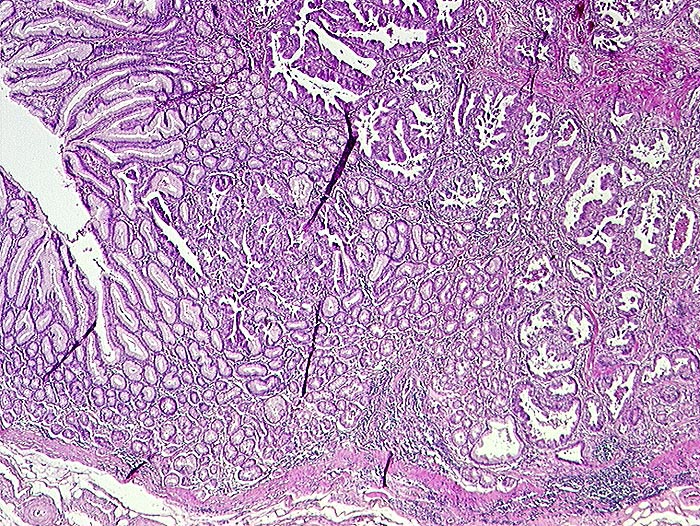

PathoPic ID 1342 - Adenokarzinom intestinaler Typ nach Lauren

Adenokarzinom intestinaler Typ nach Lauren

Magenantrum

Magenantrumschleimhaut links. Rechts davon unregelmässig geformte Tumordrüsen.